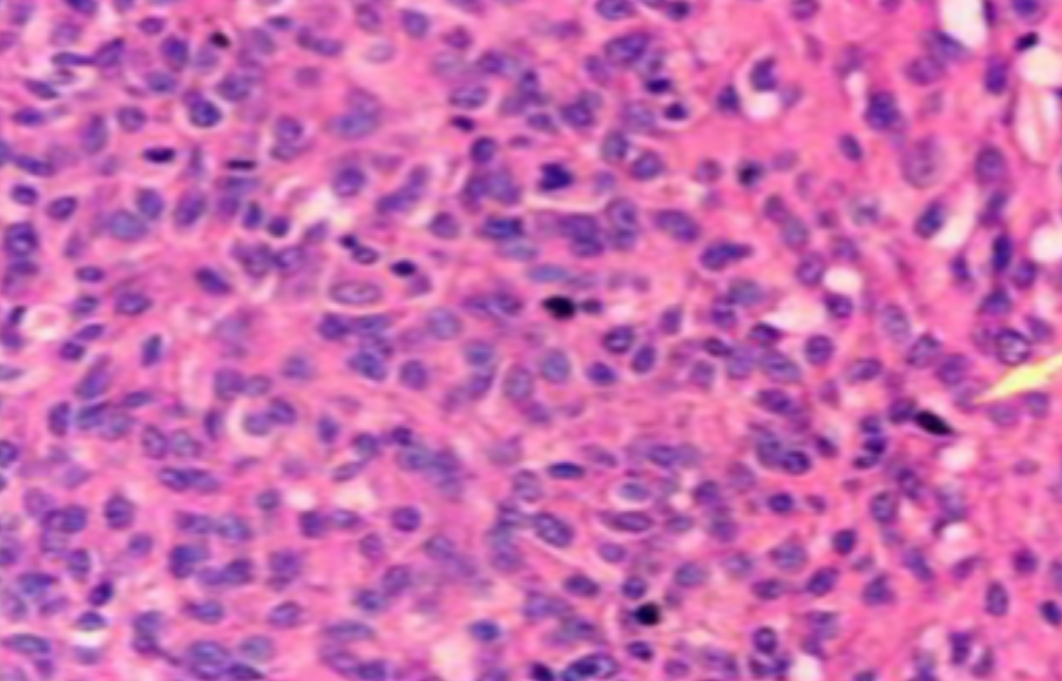

形成原因:切片经梯度乙醇处理后没有完全脱水,导致二甲苯透明、中性树胶封固后残留大量水分。 解决方法:首先移去盖玻片,用二甲苯溶解封固剂如中性树胶,再将切片置入无水乙醇内,待切片重新脱水完全后,用二甲苯透明处理,中性树胶封固。要注意所有用于脱水和透明的液体,在使用一定时间后,应及时更换。 二、细胞核呈红、棕色 形成原因:苏木精染色液过度氧化,切片在苏木精染液染色后返蓝不足。 解决方法:每次染色之前检查苏木精染色液的染色能力,发现苏木精染色液氧化过度应及时更换。此外,切片经苏木精染色后,要给切片以足够的蓝化时间,蓝化过程可用流水、温水、弱碱性溶液(如稀氨水或0.2%碳酸氢钠)等处理。 三、切片在脱蜡后出现大片白色斑点 形成原因:由于烤(烘)片温度太低,切片上的组织蜡膜在脱蜡前没有充分烤(烘)融化。或是因为切片在二甲苯液中停留时间不足,或二甲苯使用过久,造成的脱蜡不彻底。 解决方法:若是由于切片烤(烘)温度低所致,可以先用二甲苯去除切片上的封固胶,然后重新用二甲苯脱去切片上的石蜡,再进行后续染色。若是由于切片在脱蜡的二甲苯中停留时间不足或脱蜡二甲苯使用过久浓度不足所致,则需将切片退回到二甲苯中,停留较长时间,或更换二甲苯液体重新脱蜡,再入乙醇重新脱二甲苯,入0.5%盐酸水溶液褪色后,重新HE染色。 四、细胞核苍白暗淡,即苏木精染色太淡 形成原因:切片在苏木精染色液停留时间太短;苏木精染色液过度氧化,失去染色能力,不能再继续使用;分化步骤处理时间过长;固定不及时。此外值得注意的是,若骨组织细胞核暗淡,大多是脱钙过度造成的。 解决方法:切片重新染色。如果组织在酸性固定液(如Zenker、Bouin)或非中性缓冲甲醛液固定时间过长,细胞核染色能力将减弱,需增加其在苏木精染色液的时间,或用一些方法增加组织的嗜碱性,以改善细胞核的着色。例如,上述组织玻片可以使用Weigert铁苏木精染色液。如果组织是用Zenker液固定的,可将切片脱蜡后放在5%碳酸氢钠溶液3~4h,流水冲洗5min后染色。如果组织是用Bouin液固定的,可将切片脱蜡后放在5%碳酸锂1h,流水冲洗10min后染色。 五、细胞核过染,苏木精染液占据了细胞质 形成原因:玻片在苏木精染色液停留时间过长,或是切片太厚、分化步骤时间太短。 解决方法:如果不是因为切片太厚(用显微镜仔细上下微调,只有一二层细胞核层次),就需将切片进行脱色、漂白、重新染色,适当调整染色和分化时间。但如果确定是由于切片太厚导致的细胞核过染,则需要重新切片。 六、伊红着色淡 形成原因:可能是伊红染液pH值大于5,也可能是蓝化液残留过多,切片太薄,或是切片经伊红染色后在乙醇脱水时间过长。 解决方法:检查伊红染液pH值,必要的话,用乙酸将其调节在4.6~5.0之间,从而使伊红染色色彩艳丽。此外,确保每次蓝化步骤完成后,使用的弱碱性溶液被充分洗去,玻片上没有残留的弱碱性溶液。最后,检查切片的厚度,且脱水时不要让切片在低浓度乙醇中停留时间过长,因为含水多的低浓度乙醇会将切片伊红的颜色分化掉。 七、细胞质过染、分色不足 形成原因:伊红染色液浓度太高,特别是存在焰红燃料、四溴四氯荧光素钠。切片在伊红染色时间过长,或是切片在伊红染色后经乙醇脱水步骤时时间太短,而使乙醇分化伊红的作用不能产生,都能够使细胞质过染。 解决方法:适当稀释伊红染色液,减少伊红染色时间,或使切片在乙醇脱水等步骤时,停留时间相对均匀。同样,也要检查切片的厚度是否合适。 八、切片中出现蓝黑色沉淀物 形成原因:苏木精染色液中的金属膜黏附在玻片上。 解决方法:染色前仔细过滤苏木精染色液,建议使用半氧化苏木精染色液,如Gill苏木精染色液,可以避免过多的金属膜产生。 九、光镜下切片某些区域难以聚焦 形成原因:盖玻片上可能有封固切片的封固剂。 解决方法:移去盖玻片,重新用干净的盖玻片封片。检查切片封片方法,是人工手工封法,还是机器自动封法,如有问题及时调整。 十、封固剂从盖玻片与载玻片之间的缝隙回缩 形成原因:盖玻片弯曲或不平整,或是封固剂含二甲苯过多,稀释过度。 解决方法:移去盖玻片,重新找一张盖玻片,用干净的封固剂封片。如用手工封片法,保证在封固结束时,封固剂容器盖子为紧闭状态。且尽量使用小的容器盛装封固剂,一旦封固剂太黏稠,就可以选择废弃。 十一、细胞核呈灰蓝状态 形成原因:可能由于组织处理温度过高、过热,在液体石蜡中停留的时间过长。或是固定时间太短后,直接在高浓度的乙醇中进行了脱水处理。 解决方法:理论上来说,仅在组织浸蜡步骤才进行加热,组织不能在热蜡液中停留太久。如果由于某些原因不能进行下一步包埋处理,可将组织连同塑料包埋盒一并放置在室温空气中,冷却凝固,以备包埋。待需要包埋时再重新加温直至石蜡融化即可。组织在处理前必须确保固定良好,脱水最好能从低浓度的乙醇开始。 十二、类色素的点状结晶和黑色光滑细胞核 形成原因:这种裸核改变是因为切片封片前放置在空气中的时间太长,以至于二甲苯挥发,切片干燥。 解决方法:移去组织切片上的盖玻片和封固剂,重新处理。将切片水洗数分钟,然后重新脱水、透明、封固。封片过程中要保持组织切片的轻度湿润,尽量不要让其干燥。 十三、染色过淡或过浓 解决方法:如果染色过淡,可以增加染色剂的浓度、延长染色时间或更换新鲜的染色剂;如果染色过浓,则应减少染色剂的浓度或缩短染色时间。 十四、切片出现叠加褶皱 形成原因:新购买的玻片洁净度不够、用镊子撑开切片时操作不够熟练未能平整伸展,或玻片表面有油脂,切片粘贴不牢。另外,烤片时间不足、烤片温度过低或切片过厚造成切片脱落,都会造成重叠或有皱褶的情况。 解决方法:新购买的玻片最好能用硫酸清洁液浸泡一晚,然后流水冲洗干净。在适宜的温度下烤片时间宁长勿短,保证有充足的烤片时间和温度。另外,切片刀要锋利,才能切出厚薄适宜的切片,保证切片不会因为过厚而脱落。 十五、组织残缺不全或有刮划痕迹 形成原因:组织残缺不全是由于切片时修整蜡块时深度不够、组织没有全部暴露于切面。切片的刮划痕迹是由于切片刀的刀锋有缺口、包埋的组织有异物,或是钙化组织、骨组织及包埋石蜡有沙粒造成的。 解决方法:修整蜡块时保证组织块全部暴露于切面,切片时保证切片刀的锋利没刀口。同时在组织取材时去除手术异物和钙化组织。最后,骨组织要完全脱钙,这样可以保证切片的完整和平整美观。 *注:由于实验中导致结果出现误差的原因多种多样,以上内容仅供参考,具体根据实际情况进行判断。